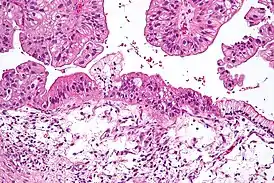

![]() Муцинозная опухоль яичника низкого потенциала злокачественности. Среднее увеличение, окраска гематоксилин-эозином. | |